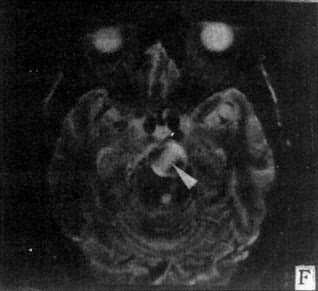

图5-1-6 MRI扫描SE序列图像

在矢状面(A)和冠状面(B)T1WI可见垂体肿块向鞍上延伸,呈等信号区(→);在横断面T1WI(C)和T2WI(D)上分别可见左枕和右基底节区脑梗塞灶呈低和高信号区(→);在矢状面T1WI(E)和横断面T2WI(F)上,可见基底动脉瘤环形影,其内为低信号和高信号区,高信号区为瘤内血栓形成(→)